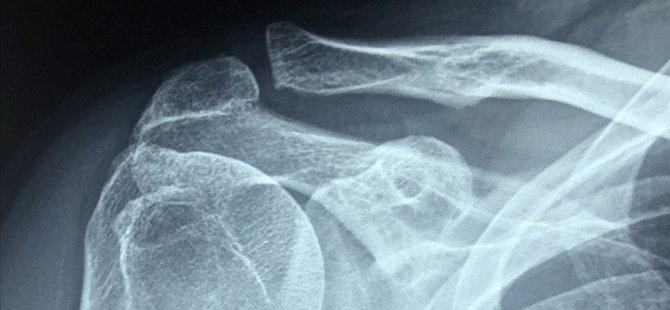

Sağlık Bilimleri Üniversitesi (SBÜ) Kanuni Sultan Süleyman Eğitim ve Araştırma Hastanesi Ortopedi ve Travmatoloji Kliniği Sorumlusu Prof. Dr. Cemil Ertürk, AA muhabirine, omuz ekleminin eşsiz bir anatomik yapısıyla vücudun en hareketli eklemi olduğunu söyledi.

Buna karşın, vücudun diğer eklemlerine göre bu eklemin sağlamlığının, kemik-kemik bağlantısından çok top ve yuva eklemini çevreleyen kapsül, tendon ve kas gibi yumuşak dokular tarafından sağlandığını ifade eden Ertürk, bu nedenle vücudun en hareketli eklemi olmasına karşın en fazla çıkma riskini de taşıyan eklem olduğunu söyledi.

Ertürk, omuzun çıkmasına engel olmak için eklemi çevreleyen yumuşak dokuların uyumlu çalışmasının son derecede önemli olduğunu, bu bölgede bir kere oluşan çıkığın daha sonra tekrarlama riskinin diğer eklemlere göre oldukça fazla olduğunu vurguladı.

İlk çıkığın 20 yaştan önce oluşması durumunda tekrarlama olasılığının yüzde 90 olduğunu belirten Ertürk, "Tekrarlayan omuz çıkıkları özellikle genç, aktif ve spor yapan genç hasta grubunda karşımıza çıkar ve 40 yaşından sonra nadiren görülür. İlk çıkık genellikle ciddi bir travma sonrası oluşur. Daha sonra özellikle 30 yaş altı hastalarda günlük aktiviteler sırasında çıkıklar oluşabilir. Çıkıkların tekrarlaması, hastanın korku duymasına, omuzunda çıkık endişesi yaşamasına ve günlük aktivitelerinde kısıtlama yapma ihtiyacı duymasına neden olabilir. Bu tip olgularda cerrahi tedavi gereklidir." diye konuştu.